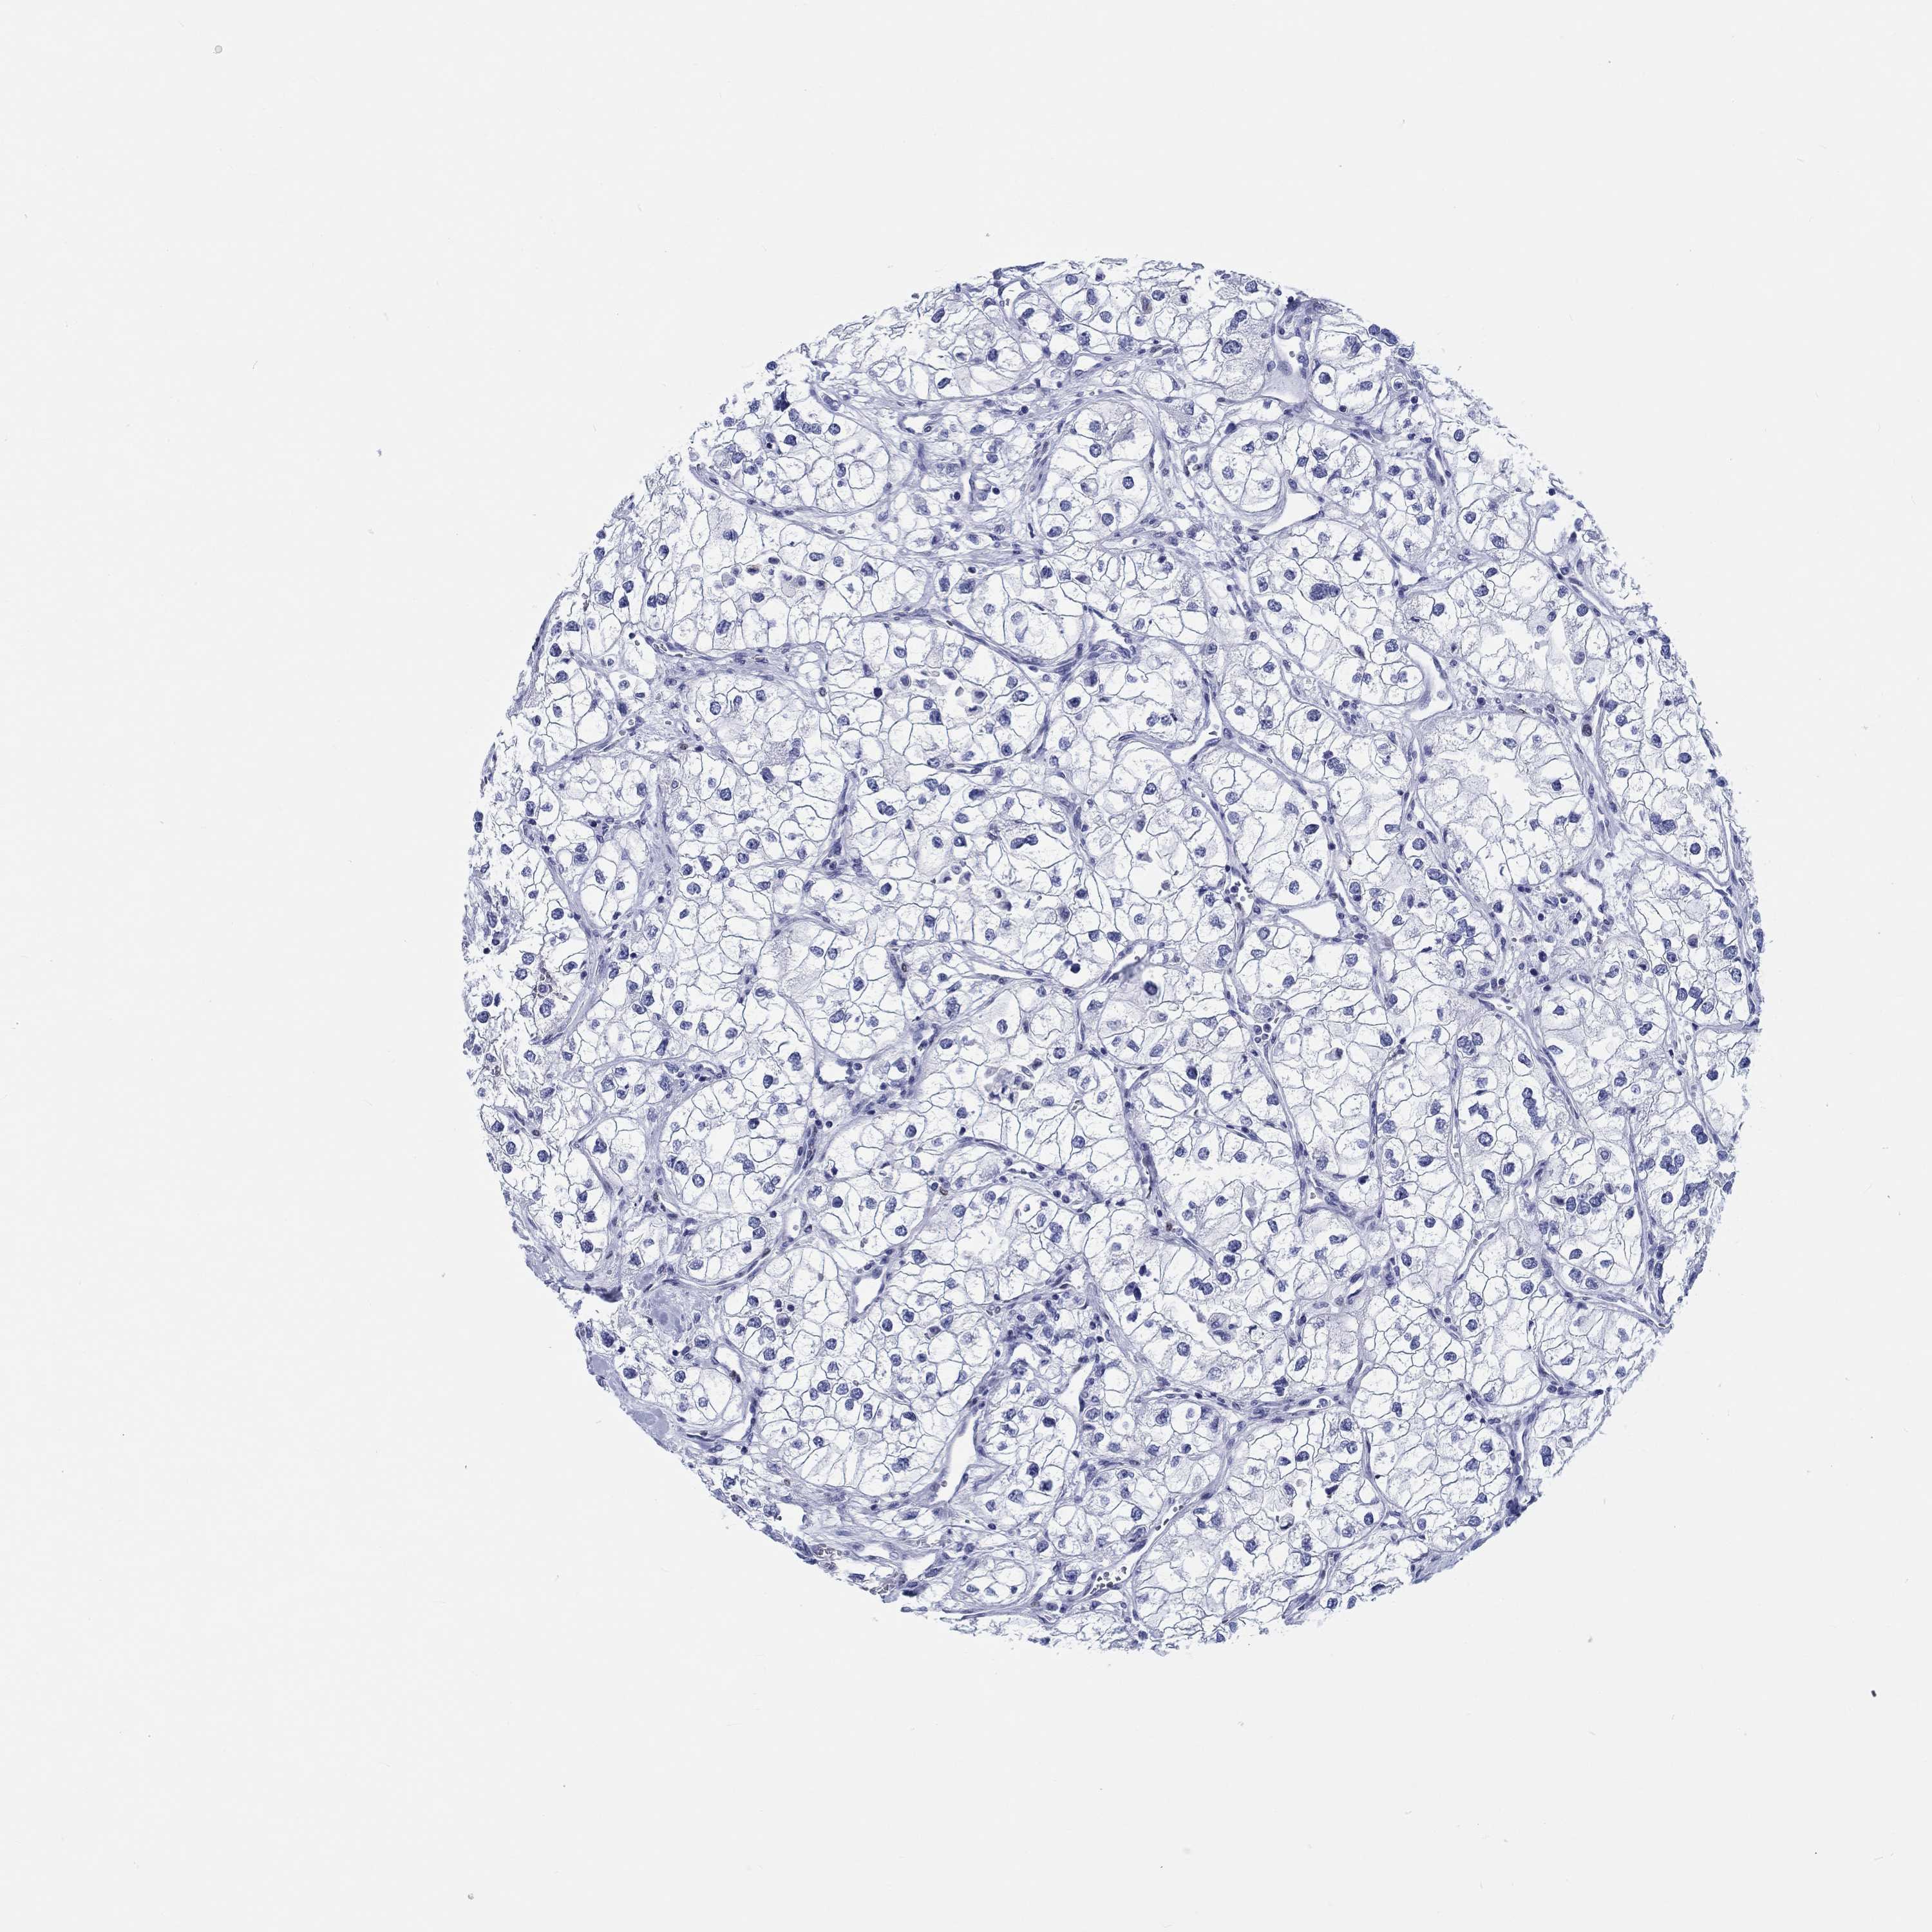

CANCER RENAL CANCER Show tissue menu

KICH TCGA KIRC TCGA KIRC VALIDATION KIRP TCGA PROTEIN RCC CPTAC PROTEIN EXPRESSION

KIDNEY RENAL CLEAR CELL CARCINOMA (VALIDATION) - Interactive survival scatter ploti

TCGA RNA samplesi

RNA-seq data is reported as average FPKM (number Fragments Per Kilobase of exon per Million reads), generated by the The Cancer Genome Atlas (TCGA) .

Normal distribution across the dataset is visualized with box plots, shown as median and 25th and 75th percentiles. Points are displayed as outliers if they are above or below 1.5 times the interquartile range. FPKM values of the individual samples are presented next to the box plot.

Average pTPM 0.0

Number of samples 100